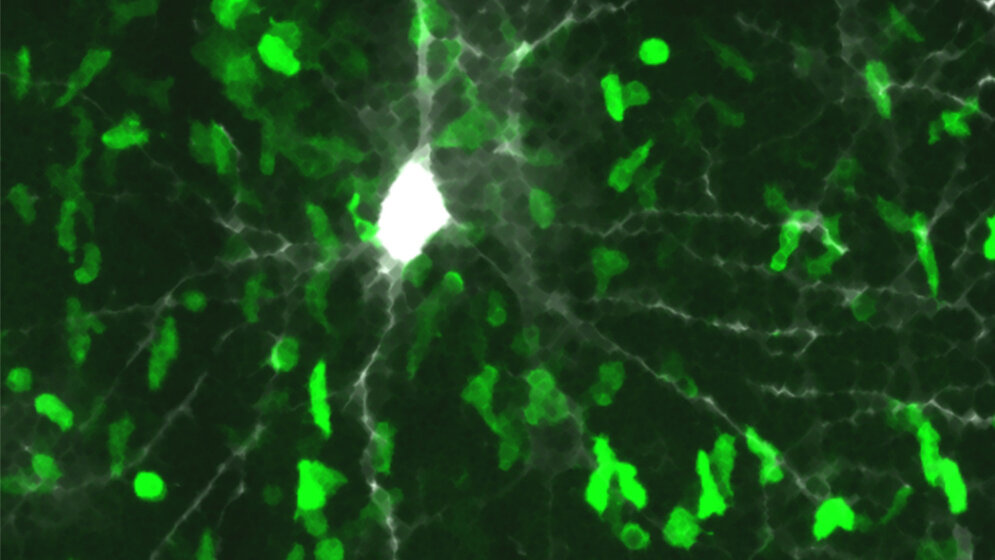

*Beta-Synuclein-erkennende T-Zellen stürmen die graue Hirnsubstanz. Zu sehen ist eine mikroskopische Aufnahme in der Hirnrinde einer Ratte. Die pathogenen T-Zellen (grün) sind in großer Zahl in das Gewebe der grauen Hirnsubstanz eingedrungen. Zum Teil bilden sie direkte Kontakte mit einer Nervenzelle und deren Fortsätzen (grau-weiß). Bild: Institut für Neuroimmunologie und Multiple-Sklerose-Forschung

„Unerwartet traten bei den Tieren neuartige neurologische Krankheitszeichen auf. Die Schädigungen sahen auch anders aus, die pathogenen Zellen drangen praktisch ausschließlich in die graue Hirnsubstanz ein“, sagt Dr. Francesca Odoardi, Institut für Neuroimmunologie und Multiple Sklerose Forschung der UMG, und Mit-Seniorautorin der Studie. Diese Entzündungsreaktionen verursachten, vor allem bei mehrfachen Schüben, irreversible Zerstörungen und ein Schrumpfen der grauen Hirnsubstanz, ähnlich wie es von der Multiple Sklerose beim Menschen bekannt ist. In der Tat konnten die Forscher im Blut von Multiple Sklerose-Betroffenen auch eine Vermehrung dieser speziellen T-Zellen finden. Diese waren besonders bei Patienten mit fortschreitendem Krankheitsverlauf erhöht.

Immunzellen, die gegen das in Nervenzellen vorkommende Eiweiß beta-Synuklein gerichtet sind, dringen gezielt in das Steuerzentrum des Gehirns ein und lösen vor Ort eine Entzündungsreaktion aus. Dadurch werden die hochspezialisierten und zarten Nervengeflechte geschädigt. Die fatale Folge: Das Gehirn schrumpft, und es kommt zu nicht reparierbaren neurologischen Ausfällen. Die Göttinger Wissenschaftler entdeckten zudem, dass solche zerstörerischen Immunzellen vor allem im Blut von Multiple Sklerose-Erkrankten mit einem fortschreitend-chronischen Verlauf vermehrt sind. Diese Erkenntnisse könnten für diagnostische oder therapeutische Aspekte bei der Multiplen Sklerose von Bedeutung sein.